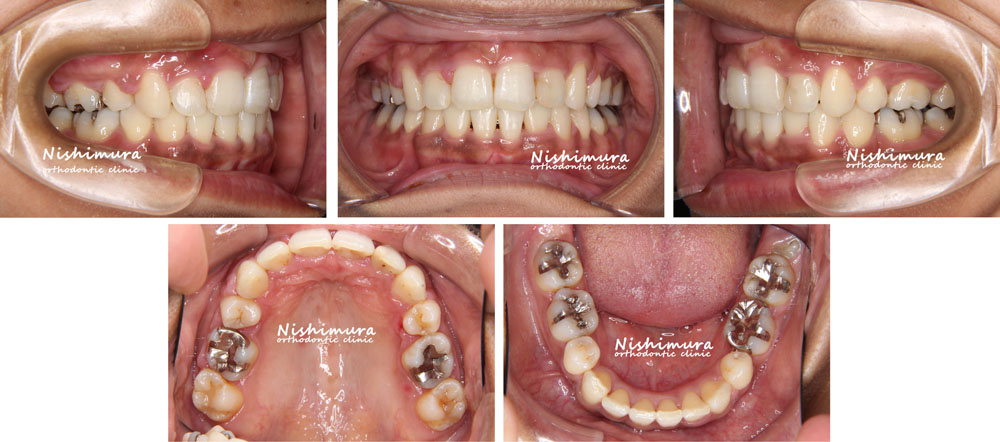

治療前

治療前の写真

治療後

治療後の写真